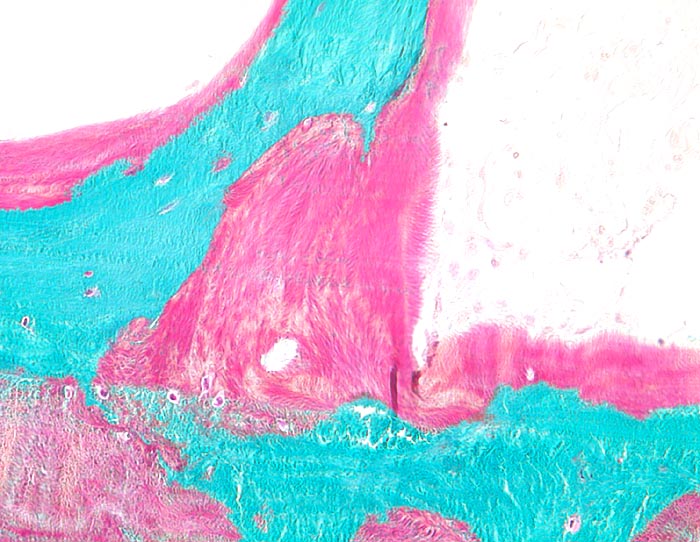

Bei Vitamin D Mangel ist das Gesamtvolumen sowie die Menge des Osteoids auf der Oberfläche der Spongiosabälkchen vermehrt (Volumen- bzw. Oberflächenosteoidose). Wechselt das Angebot an Vitamin D, kann unmineralisiertes Osteoid auch von mineralisierter Matrix eingeschlossen werden (= begrabenes Osteoid ( 3517)). Verbreiterte Osteoidsäume können neben der Osteomalazie (bzw. der Rachitis im Kindesalter) auch bei Hyperparathyreoidismus, bei einer fibrösen Dysplasie oder bei schnell wachsenden knochenbildenden Tumoren beobachtet werden. Insbesondere bei metabolischer Ursache sind die histologischen Veränderungen häufig kombiniert mit Veränderungen einer Fibroosteoklasie, bei der es zu oft tunnelierenden osteoklastären Resorptionen des Knochens und konsekutiver Auffüllung mit einem gut vaskularisierten bindegewebigen Stroma kommt. Die radiologisch nachweisbaren Looser-Umbauzonen (benannt nach dem Schweizer Chirurgen E. Looser) entsprechen Arealen unvollständig durchgebauter Fissuren/Frakturen mit nicht mineralisiertem Faserknochen. Durch eine Tetrazyklinmarkierung in zeitlich definiertem Abstand vor einer Knochenbiopsie kann die Mineralisationsdynamik abgeschätzt werden, da Tetrazykline bei der Mineralisation in den Knochen miteingebaut werden und im Fluoreszenzmikroskop identifiziert werden können.